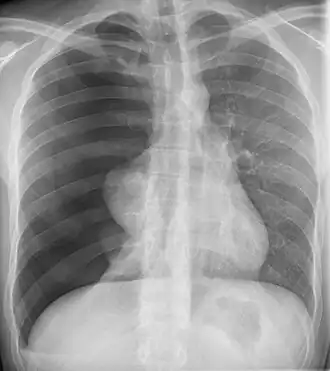

![]() Radiografía de un neumotórax. La amplia mayoría de los neumotórax catameniales ocurren en el lado derecho, al igual que en este caso. | ||

El neumotórax catamenial es un neumotórax espontáneo que recurre durante la menstruación, dentro de las 72 horas anteriores o posteriores al inicio de un ciclo. Es una de las manifestaciones clínicas de la endometriosis torácica. Se caracteriza por producirse, a las pocas horas o días de comenzar la menstruación, un neumotórax —acumulación de aire entre el pulmón y la serosa que lo rodea, la pleura—.[2] Aunque se asocia con la presencia de tejido endometrial en el tórax, no es un hallazgo histológico constante en las personas afectadas. Según la fuente, entre un 87.5 % y un 100 % de los casos ocurren en el pulmón derecho.[2] El tratamiento consiste en suprimir la secreción de estrógenos por parte del ovario, por ejemplo con anticonceptivos orales, o en cirugía de tórax.[3]

Casi el 90% de los casos ocurren en el hemitórax derecho, un fenómeno que se cree que podría deberse a la dirección del flujo del líquido retroperitoneal. El flujo peritoneal sigue un patrón en sentido horario, lo que probablemente podría explicar la tendencia de los neumotórax catameniales a ser del lado derecho. Los defectos en el diafragma que se encuentran con frecuencia en los individuos afectados podrían proporcionar una vía de entrada, al igual que la micro embolización a través de las venas pélvicas. Tales defectos diafragmáticos pueden ser congénitos o adquiridos.[cita requerida]